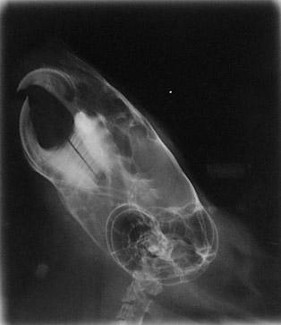

Below are x-rays of both a normal chinchilla and a chinchilla with malocclusion.

Maloccluded

The maloccluded x-ray shows overgrowth of both the roots and the crowns. There is no clear line where the upper and lower teeth meet. Also, the roots are growing both out of the lower jaw and into the eye sockets.